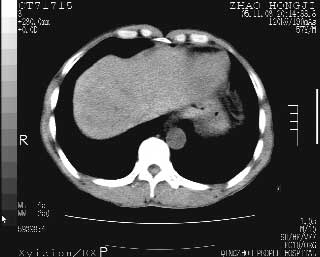

临床资料:男性,57岁,上腹部疼痛并5天,突然加重并延及全腹伴恶心5小时入院。胰淀粉酶化验在正常范围。检查:腹肌紧张,全腹压痛、反跳痛,尤以右上腹部为著。肠鸣音减低。血常规:wbc14.6x10/9, n:11.3x10/9 ,血压:135/90mmhg. 胸部透视:腹部肠腔轻度张气,未见其它异常改变。

肝右前缘少量积气,其他未见明显异常.考虑上消化道穿孔.

小网膜囊积气液,胃壁僵硬。考虑胃穿孔。

小膜网膜积液,肝缘气腹征,上消化道穿孔。

肝缘见少许气体,胰尾部见少许气体包饶(蓝色圈),12指肠上部或球部邻近胆囊周边也可见少许气体影(黄色圈),并忖托出胆囊壁,12指肠远段肠道内未见明显气体(白色箭)。

肝脏前缘见少量积气、胰尾部见少许气体包饶,肾前筋膜未见增厚,临床淀粉酶不高,意见:上消化道穿孔。

关于本病例的术后诊断:

入院3小时后行剖腹探查术,见腹腔内大量脓性混浊液约1000ml,十二指肠球部溃疡穿孔,溃疡面约2.5x2cm,穿孔直径约0.6cm。胃内容物外益,周围组织炎性水肿明显。行十二指肠穿孔修补术。术后诊断:

1、十二指肠溃疡穿孔

2、弥漫性腹膜炎

对于少量的腹腔游离气体,ct检查较普通透视有绝对的优势,它不仅可以看到肝脏前上缘的气体,而且还能够看到小网膜区的游离气体。从而可以肯定诊断。各位分析战友的很好,感谢大家的参入!